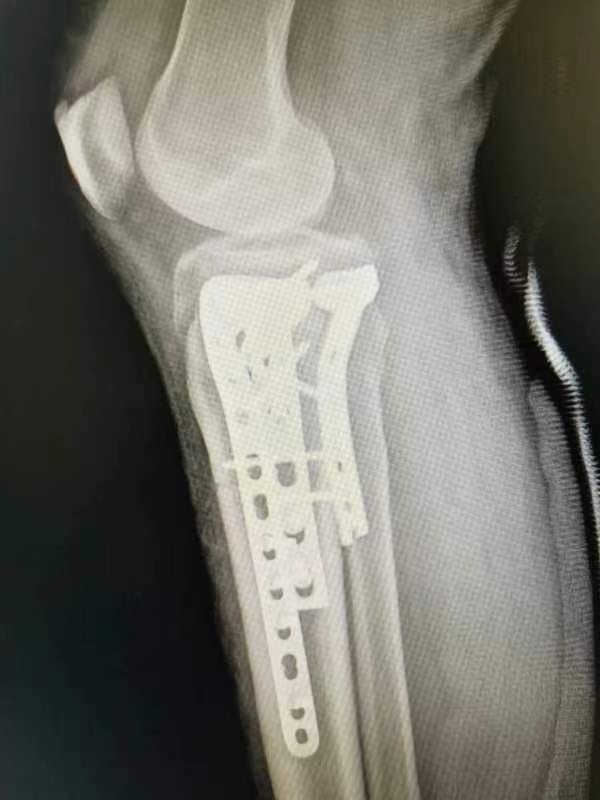

胫骨平台粉碎性骨折术前术后